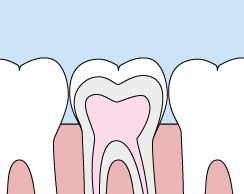

Crowns

Crowns are a cosmetic restoration used to improve your tooth’s shape or to strengthen a tooth. Crowns are most often used for teeth that are broken, worn, or have portions destroyed by tooth decay.

A crown is a "cap" that is cemented onto an existing tooth and usually covers the portion of that tooth above the gum line. In effect, the crown becomes your tooth’s new outer surface. Crowns can be made of porcelain, metal, or both. Porcelain crowns are most often preferred because they mimic the translucency of natural teeth and are very strong.

Crowns or onlays (partial crowns) are needed when there is insufficient tooth strength remaining to hold a filling. Unlike fillings, which apply the restorative material directly into your mouth, a crown is fabricated away from your mouth. Your crown is created from your unique tooth impression in a lab. This allows a dental laboratory technician to examine all aspects of your bite and jaw movements. Your crown is then sculpted just for you so that your bite and jaw movements function normally once the crown is placed.